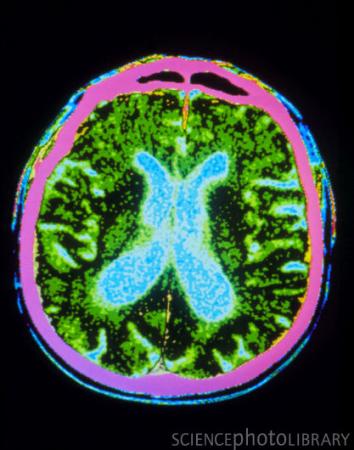

帕金森综合症病人脑部CT扫描彩图(图)

在患有帕金森综合症病人的大脑植入刺激用的移植物后,在随访的10年间里,他们在行动能力上能持续恢复,但移植后其它部分功能上的恢复会随着时间延长而逐渐消失。该研究的论文发表在最近的JAMA杂志的子刊《Archives of Neurology》上。